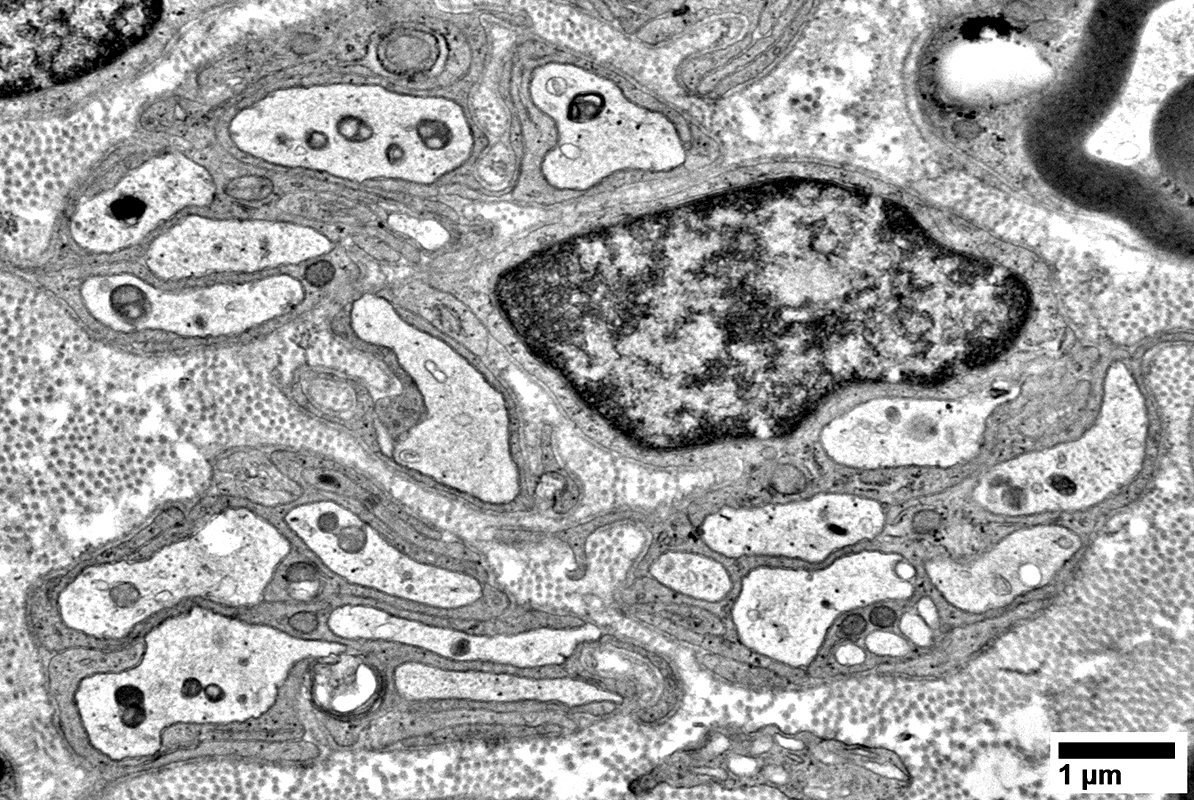

Non-Myelinating Schwann Cells & Unmyelinated Small Axons

Unmyelinated Axons

Numbers: Relatively preserved; Several per Schwann cell

Non-myeliinating Schwann cells

May have pale cytoplasm (Below)

From: R Schmidt